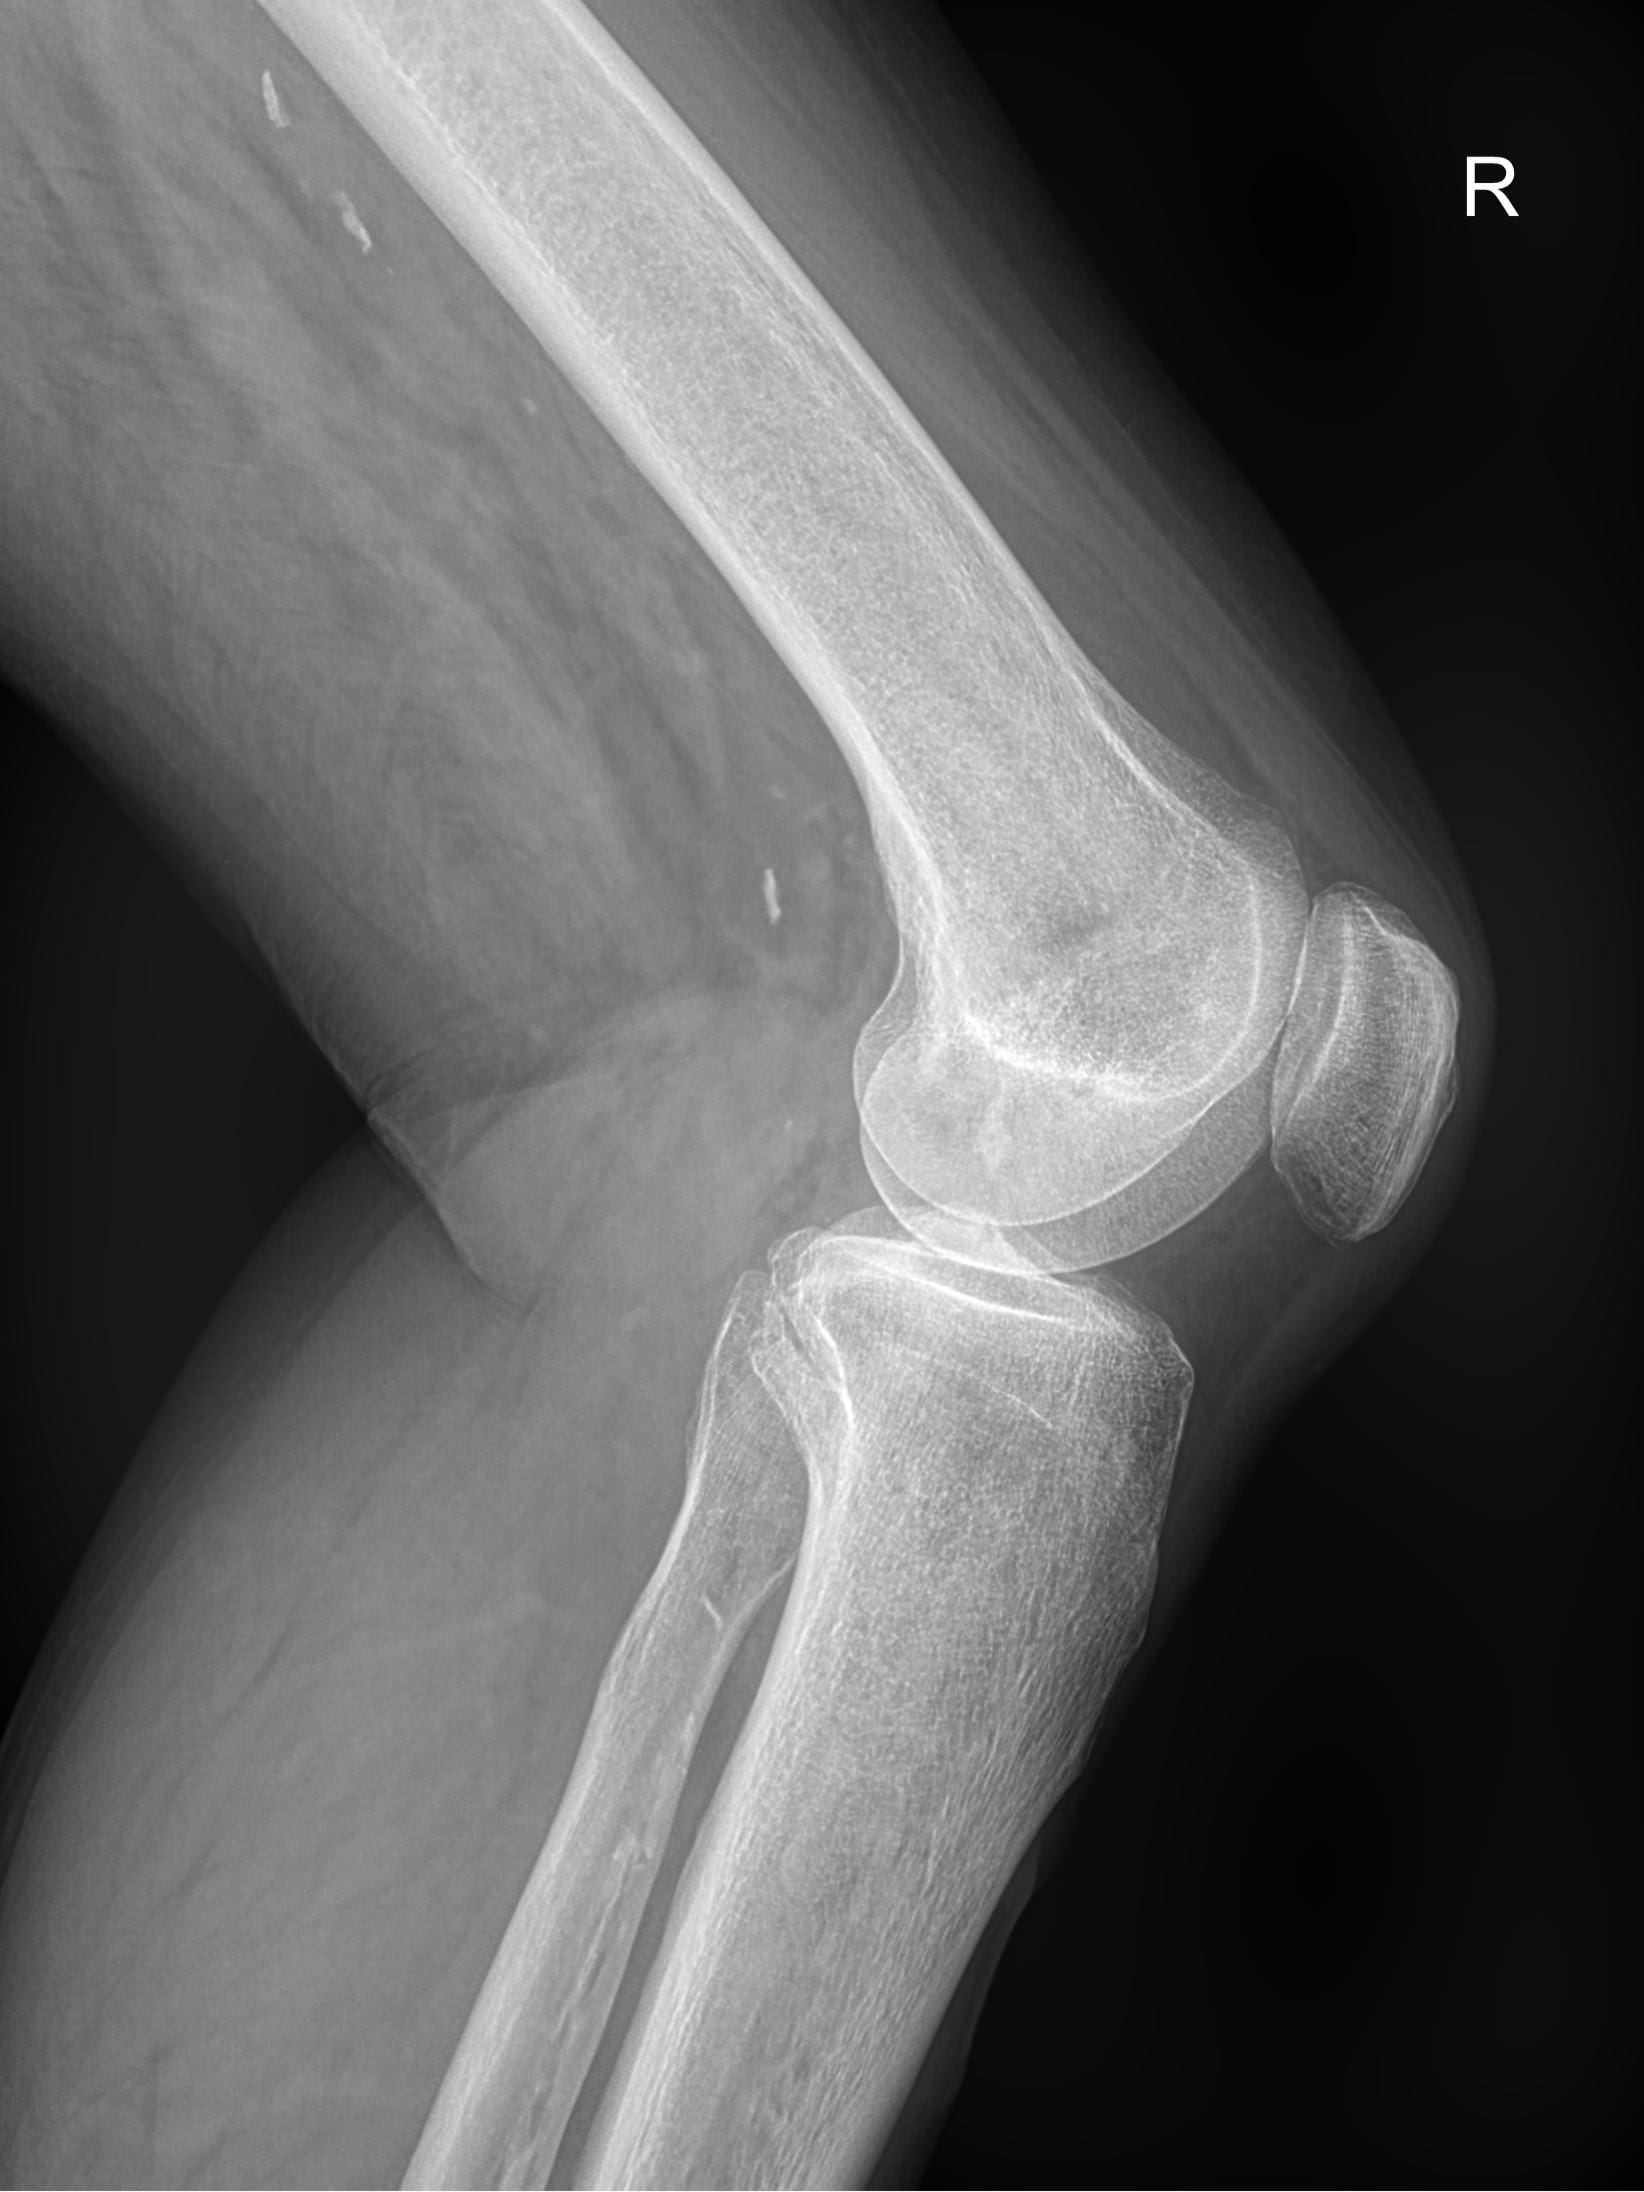

Рентген ― самый простой и быстрый метод диагностики поражения коленных суставов. Это неинвазивный и безболезненный , а также высокоинформативный способ увидеть внутреннее состояние колена. Современное рентгеновское оборудование использует минимально возможную дозу облучения. При этом на рентгенограмме отчетливо просматриваются части бедренной, малоберцовой и большеберцовой костей, надколенник, а также мягкие ткани вокруг них.

На рентгенограмме будут видны элементы сустава и патологические изменения в них:

• Суставная щель ― может быть расширена или сужена, причем неравномерно, иметь выпот, выросты, костные и хрящевые обломки;

• Соответствие друг другу суставных поверхностей ― естественное или вывих;

• Положение надколенника ― может быть неестественным;

• Состояние костной ткани: перелом, разрежение, уплотнение, размягчение, склерозирование;

• Мягкие ткани ― нормальные или отекшие, с инородными телами.